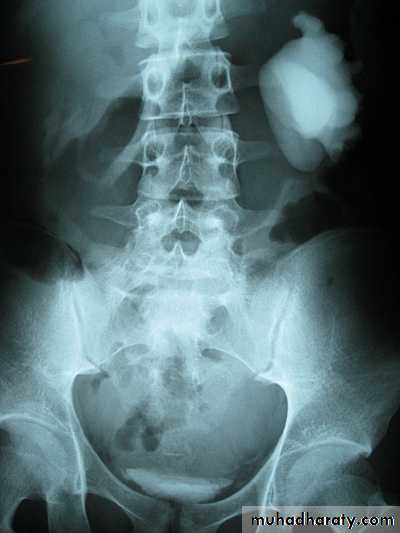

17- Ectopic + hydronephrosis

19- Ectopic + hydronephrosis